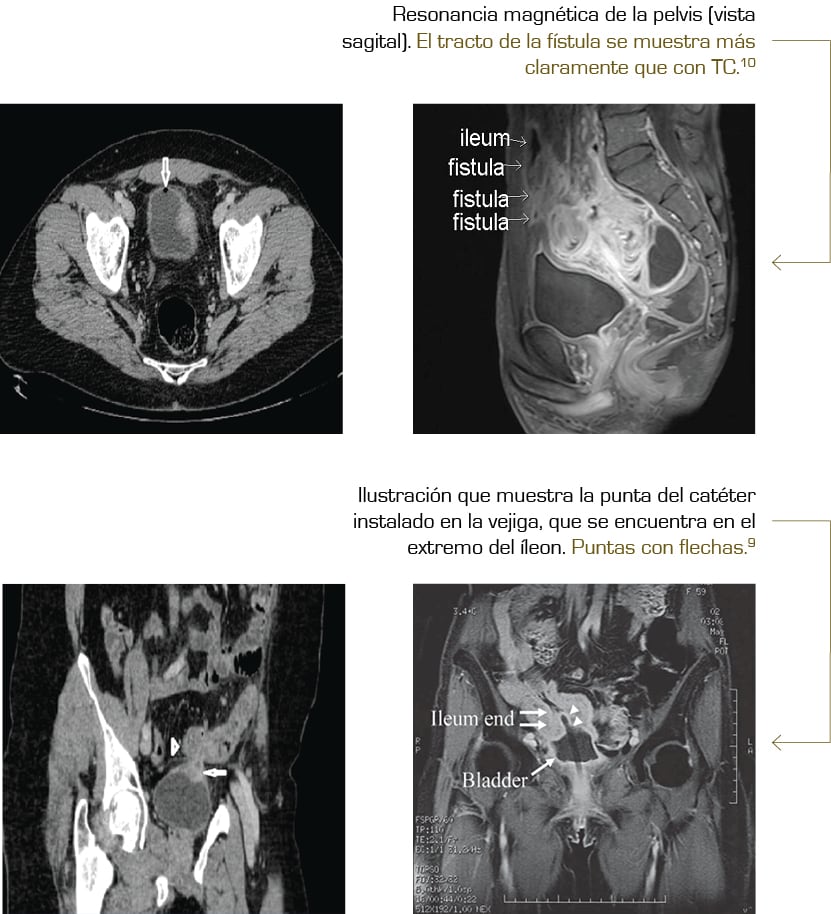

La fístula que provoca la fecaluria puede diagnosticarse a partir de exámenes con imágenes como: tomografía computarizada, un enema de contraste, fluoroscopia, cistoscopia, prueba de Bourne o una biopsia.